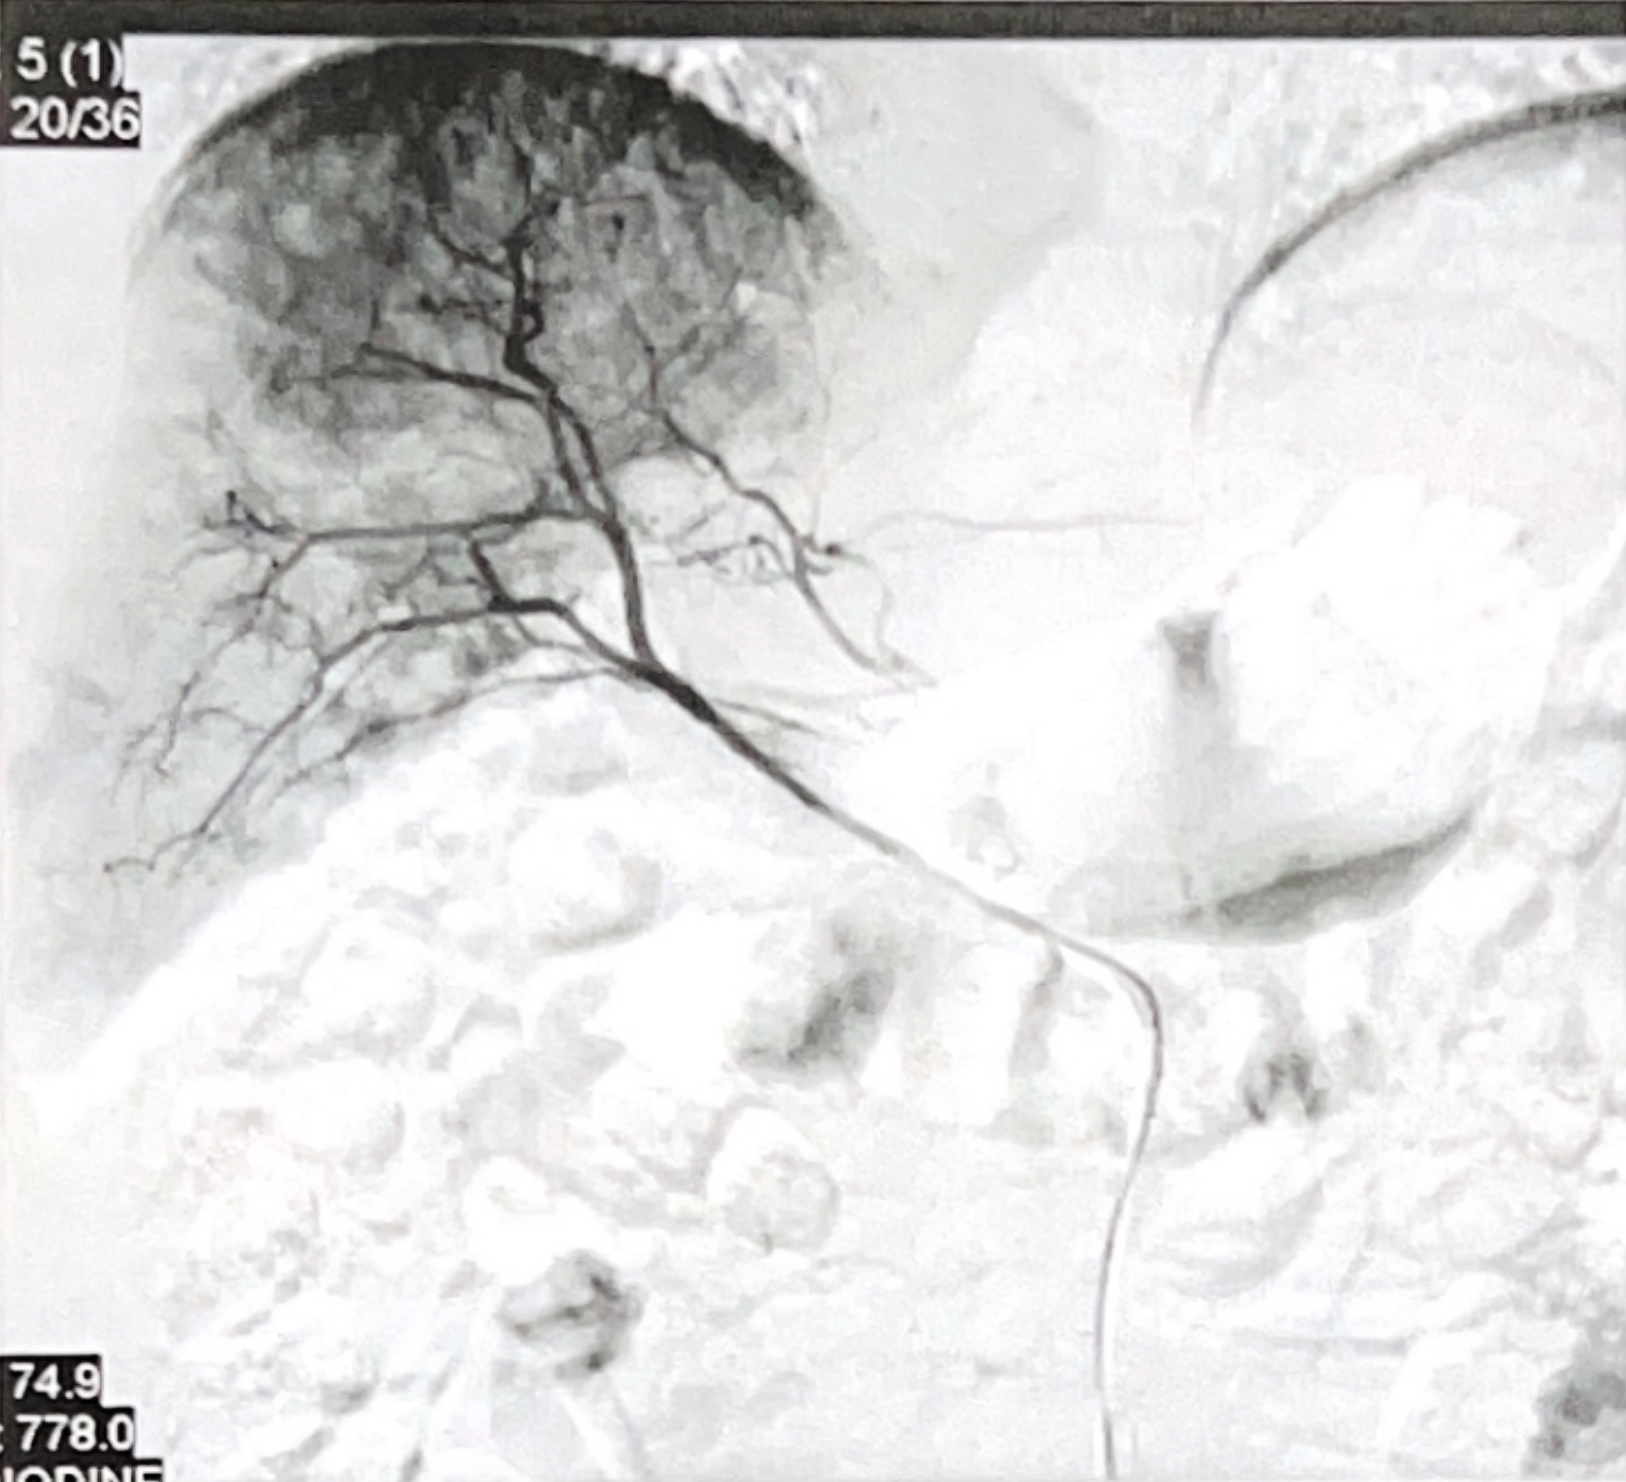

Transarterial Chemoembolization for The Liver LesionSystemic therapy is important for managing metastatic disease. However, prioritizing local control can be beneficial, especially when a significant tumor is present in the liver. This approach can help reduce the tumor size or slow its growth. Therefore, transarterial chemoembolization (TACE) was recommended as a potential treatment option.

Transarterial chemoembolization (TACE) is an interventional oncology procedure that delivers chemotherapy directly into the arteries supplying a liver tumor. By administering the drugs directly to the tumor's blood supply and then blocking these vessels, the treatment maximizes the chemotherapy's effect within the liver while minimizing its systemic circulation.

In Miguel's case, the TACE procedure utilized the drugs Mitomycin and Cisplatin. The goal was to perform a targeted, locoregional treatment of the liver metastasis, conducted by a team of specialists in image-guided tumor therapies.